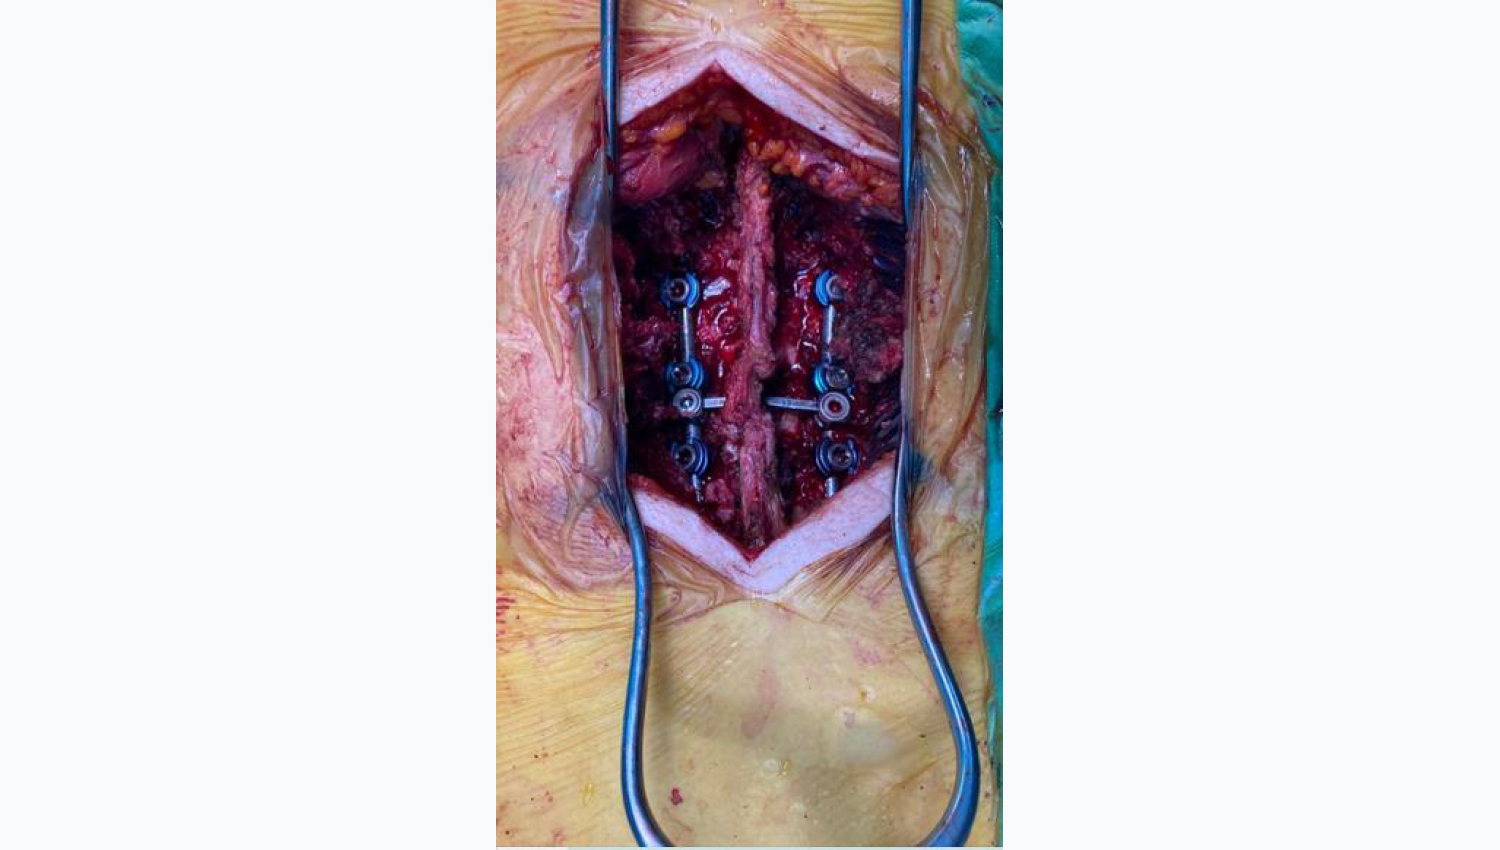

2.Metrosan- Ligamed Cannulated Posterior Polyaxial Screws(50x45, 50x40,45x50) are prepared for implanting.

3.The implantation of the Metrosan- Ligamed cannulated posterior Polyxiaal Screw has been completed.

4.The Powerbone Flexible Graft is cut to the required dimensions for implantation and wetted with the patient's blood and implantation is performed. After mixing the Powerbone Bone Cement product, it was implanted in the relevant area.

5.Final clinical view.